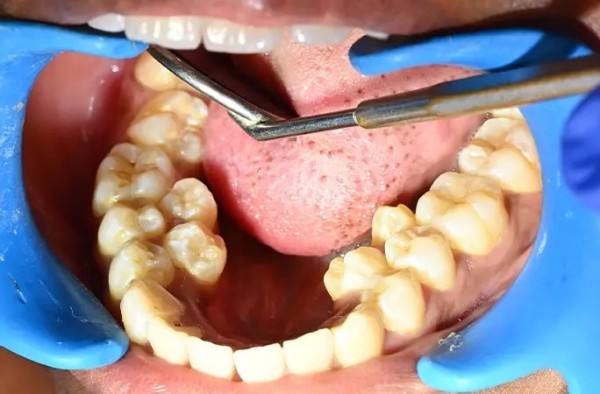

У девушки на шесть зубов больше, чем у большинства людей: у жительницы Индии насчитали 38 зубов вместо 32-ух. При этом у неё нашли ещё два зуба, которые не прорезались. Больше только у мужчины из Канады — 41 штука.